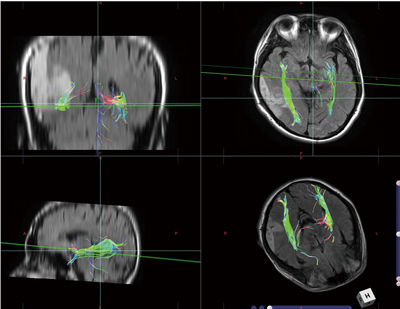

症例1(視放線症例)

右側頭葉の悪性グリオーマの症例。両側の視放線の後半部 (Meyer's loop) を描出している。背景のFLAIR像で高信号を示す腫瘍により患側の視放線は内方に偏位しているが、線維路の描出は健側と比べ同程度であることがわかる。